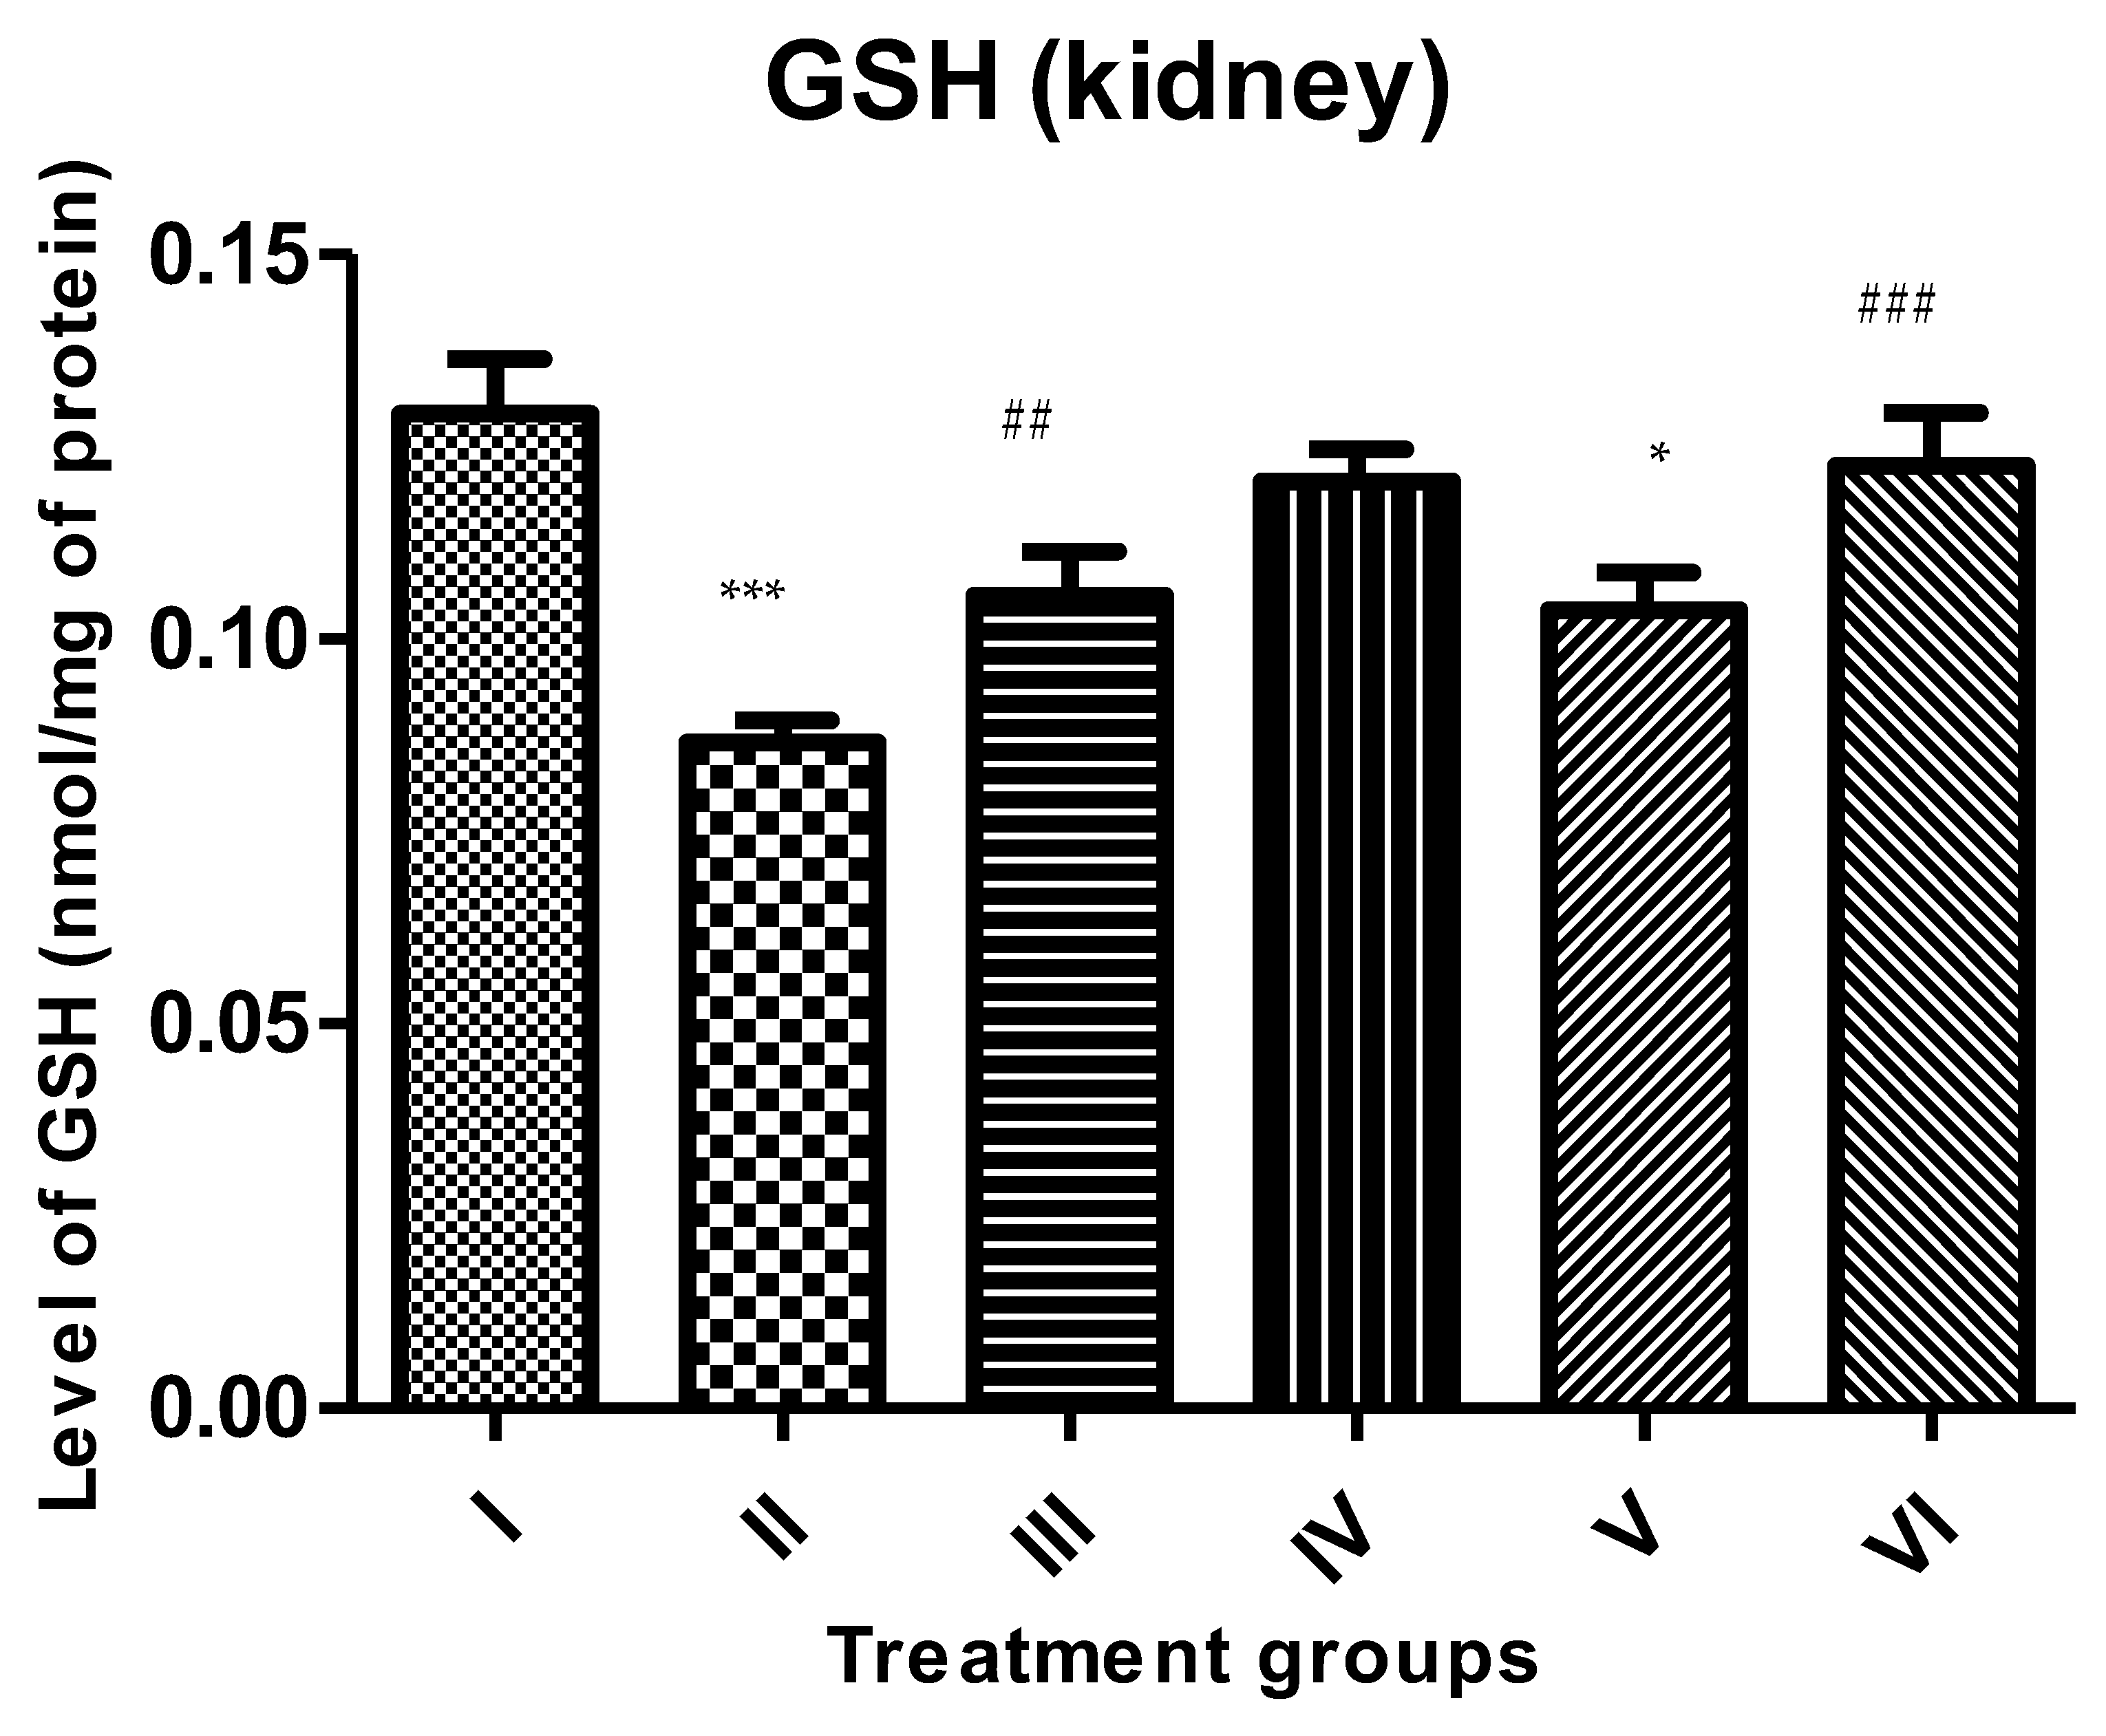

2.4.4. GSH